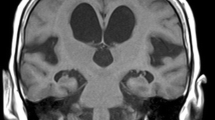

The locations of the clusters were determined first by using the Harvard-Oxford Subcortical Structural Atlas and JHU ICBM-DTI-81 White-Matter Labels (implemented in FSLView, http://www.cma.mgh.harvard.edu/fsl_atlas.html). However, there was insufficient accuracy for warping from the MNI space (Fig. 1a), such that two neurologists (S.K. and E.M.) eventually identified the locations of the clusters by consulting with each other and using the mean colour-coded FA skeleton map (directionally encoded) and the mean normalized b0 image in reference to the MRI atlas of Human White Matter made by Mori et al. [28].

Comparison of skeletons and mis-registrations observed in TBSS analysis. a Demonstrates the mean FA skeleton (green) derived from the study (the comparison between the patients with INPH and the healthy control subjects) and the FMRIB58 FA standard space skeleton (grey). The periventricular tracks in the mean FA skeleton (the internal capsules and the corpus callosum in particular) are out of position. b Shows a sample of mis-registration that occurred in the comparison of MD maps between the patients with INPH and the healthy control subjects. The back-projected voxels (red) in the columns, bodies, and crura of the bilateral fornixes were positioned on each side of the lateral ventricle, and those in a peri-Sylvian portion of the SWM of bilateral frontal operculums were on each side of the Sylvian fissure. A anterior, I inferior, L left, P posterior, S superior

To confirm whether the results of TBSS analyses were based on accurate registrations, the back-projection in TBSS was performed. The back-projection can investigate where one or more voxels of the mean FA skeleton originally came from in each subject’s FA map. Two neurologists (S.K. and E.M.) examined the clusters independently to determine whether the back-projected TBSS results were positioned on tract-centre points and were anatomically the same among the patients with INPH and the HC subjects. If both neurologists judged that some clusters in the back-projected TBSS results were positioned on the outside of tract-centre points or were different among the patients with INPH, these clusters were excluded from the data set for significant regions. In addition, anatomical ROI analyses of the regions in which FA or MD were significantly altered after shunt placement were performed using a paired two-tailed Student’s t test to validate the results of the TBSS analyses. Statistical significance was defined for p values <0.05 (using Bonferroni correction).

In the present study, we investigated the differences between shunt responders and non-responders after shunt placement by applying the TBSS including back-projection and hemispheric DTI analyses to elucidate brain white matter changes in INPH patients with shunt placement. We showed that FA values in the corona radiata were decreased by shunt placement in patients that had a good response to shunt treatment. In the back-projection analysis of the TBSS, mis-registration was observed in the periventricular or intraventricular structures such as the fornix, hippocampal part of the cingulum, perithalamic area, and peri-Sylvian SWM. These regions appear to be strongly associated with the typical deformation of the brain in patients with INPH [30]. The back-projected voxels in the fornix, cingulum, and perithalamic area were positioned on each side of lateral ventricle. These findings of mis-registration were also reported in the previous INPH study applying the TBSS analysis [15]. Hattori et al. speculated that the fornix might be displaced by the elevated and stretched corpus callosum because the fornix is attached to the posterior part of the body and splenium of the corpus callosum [15]. Not only the ventricles but also the Sylvian fissures are commonly dilated in INPH, which might cause inhibition of lateral expansion of the lateral ventricles represented by the narrowing of the callosal angle [31, 32]. The dilation of the Sylvian fissures might be one cause of the elevation of the corpus callosum.